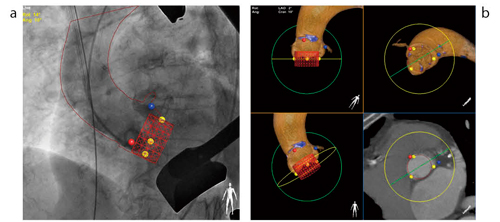

このHybrid ORシステムを用いて施行される治療法の1つが,TAVIである。現在,治験も実施されているTAVIは大動脈弁狭窄症に対するカテーテルを用いた治療法で,手術適応にならない症例へのアプローチ法として注目されている。この手技では,透視上でデバイスを留置する際,大動脈弁の位置を正確に把握することが難しく,冠動脈閉塞や大動脈弁輪破裂の危険性も指摘されている。

その中で,より安全に手技をサポートするために開発されたのが,“Heart Navigator”である。Heart Navigatorは,術前に心臓CTの3Dデータから病変部の計測と術前アングルのシミュレートを行うプランニング機能を有している。プランニングした大動脈弁,冠動脈起始部,石灰化,およびデバイスは,透視画像上に重ね合わせることができる(図6)。デバイス留置をより正確に支援するアプリケーションとして期待されている。

図6 Heart Navigator a:透視画像上に大動脈弁,冠動脈起始部,石灰化およびデバイスを重ね合わせる。 b:術前プランニング。大動脈弁,冠動脈起始部,石灰化およびデバイスを抽出

a:透視画像上に大動脈弁,冠動脈起始部,石灰化およびデバイスを重ね合わせる。

b:術前プランニング。大動脈弁,冠動脈起始部,石灰化およびデバイスを抽出